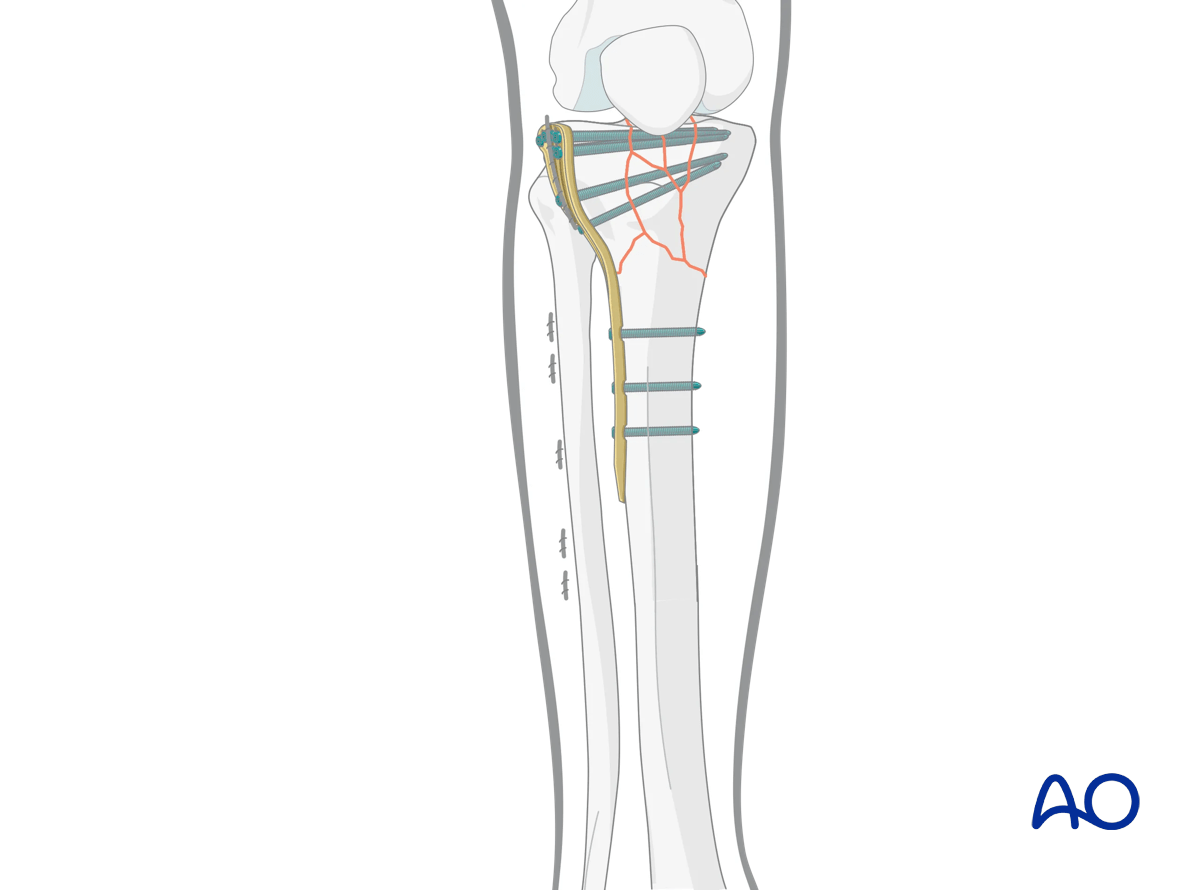

6. Plate insertion

Once the fracture is provisionally reduced the plate may be placed in an antegrade, submuscular fashion. Plates with a blunt, beveled distal end do not require pathway preparation along the lateral aspect of the tibia. In some situations, the passage of a Cobb elevator may facilitate subsequent plate placement.

Some systems have an outrigger that facilitates minimally invasive surgery, and allows the insertion of percutaneous self-drilling, self-tapping screws in the metadiaphysis.